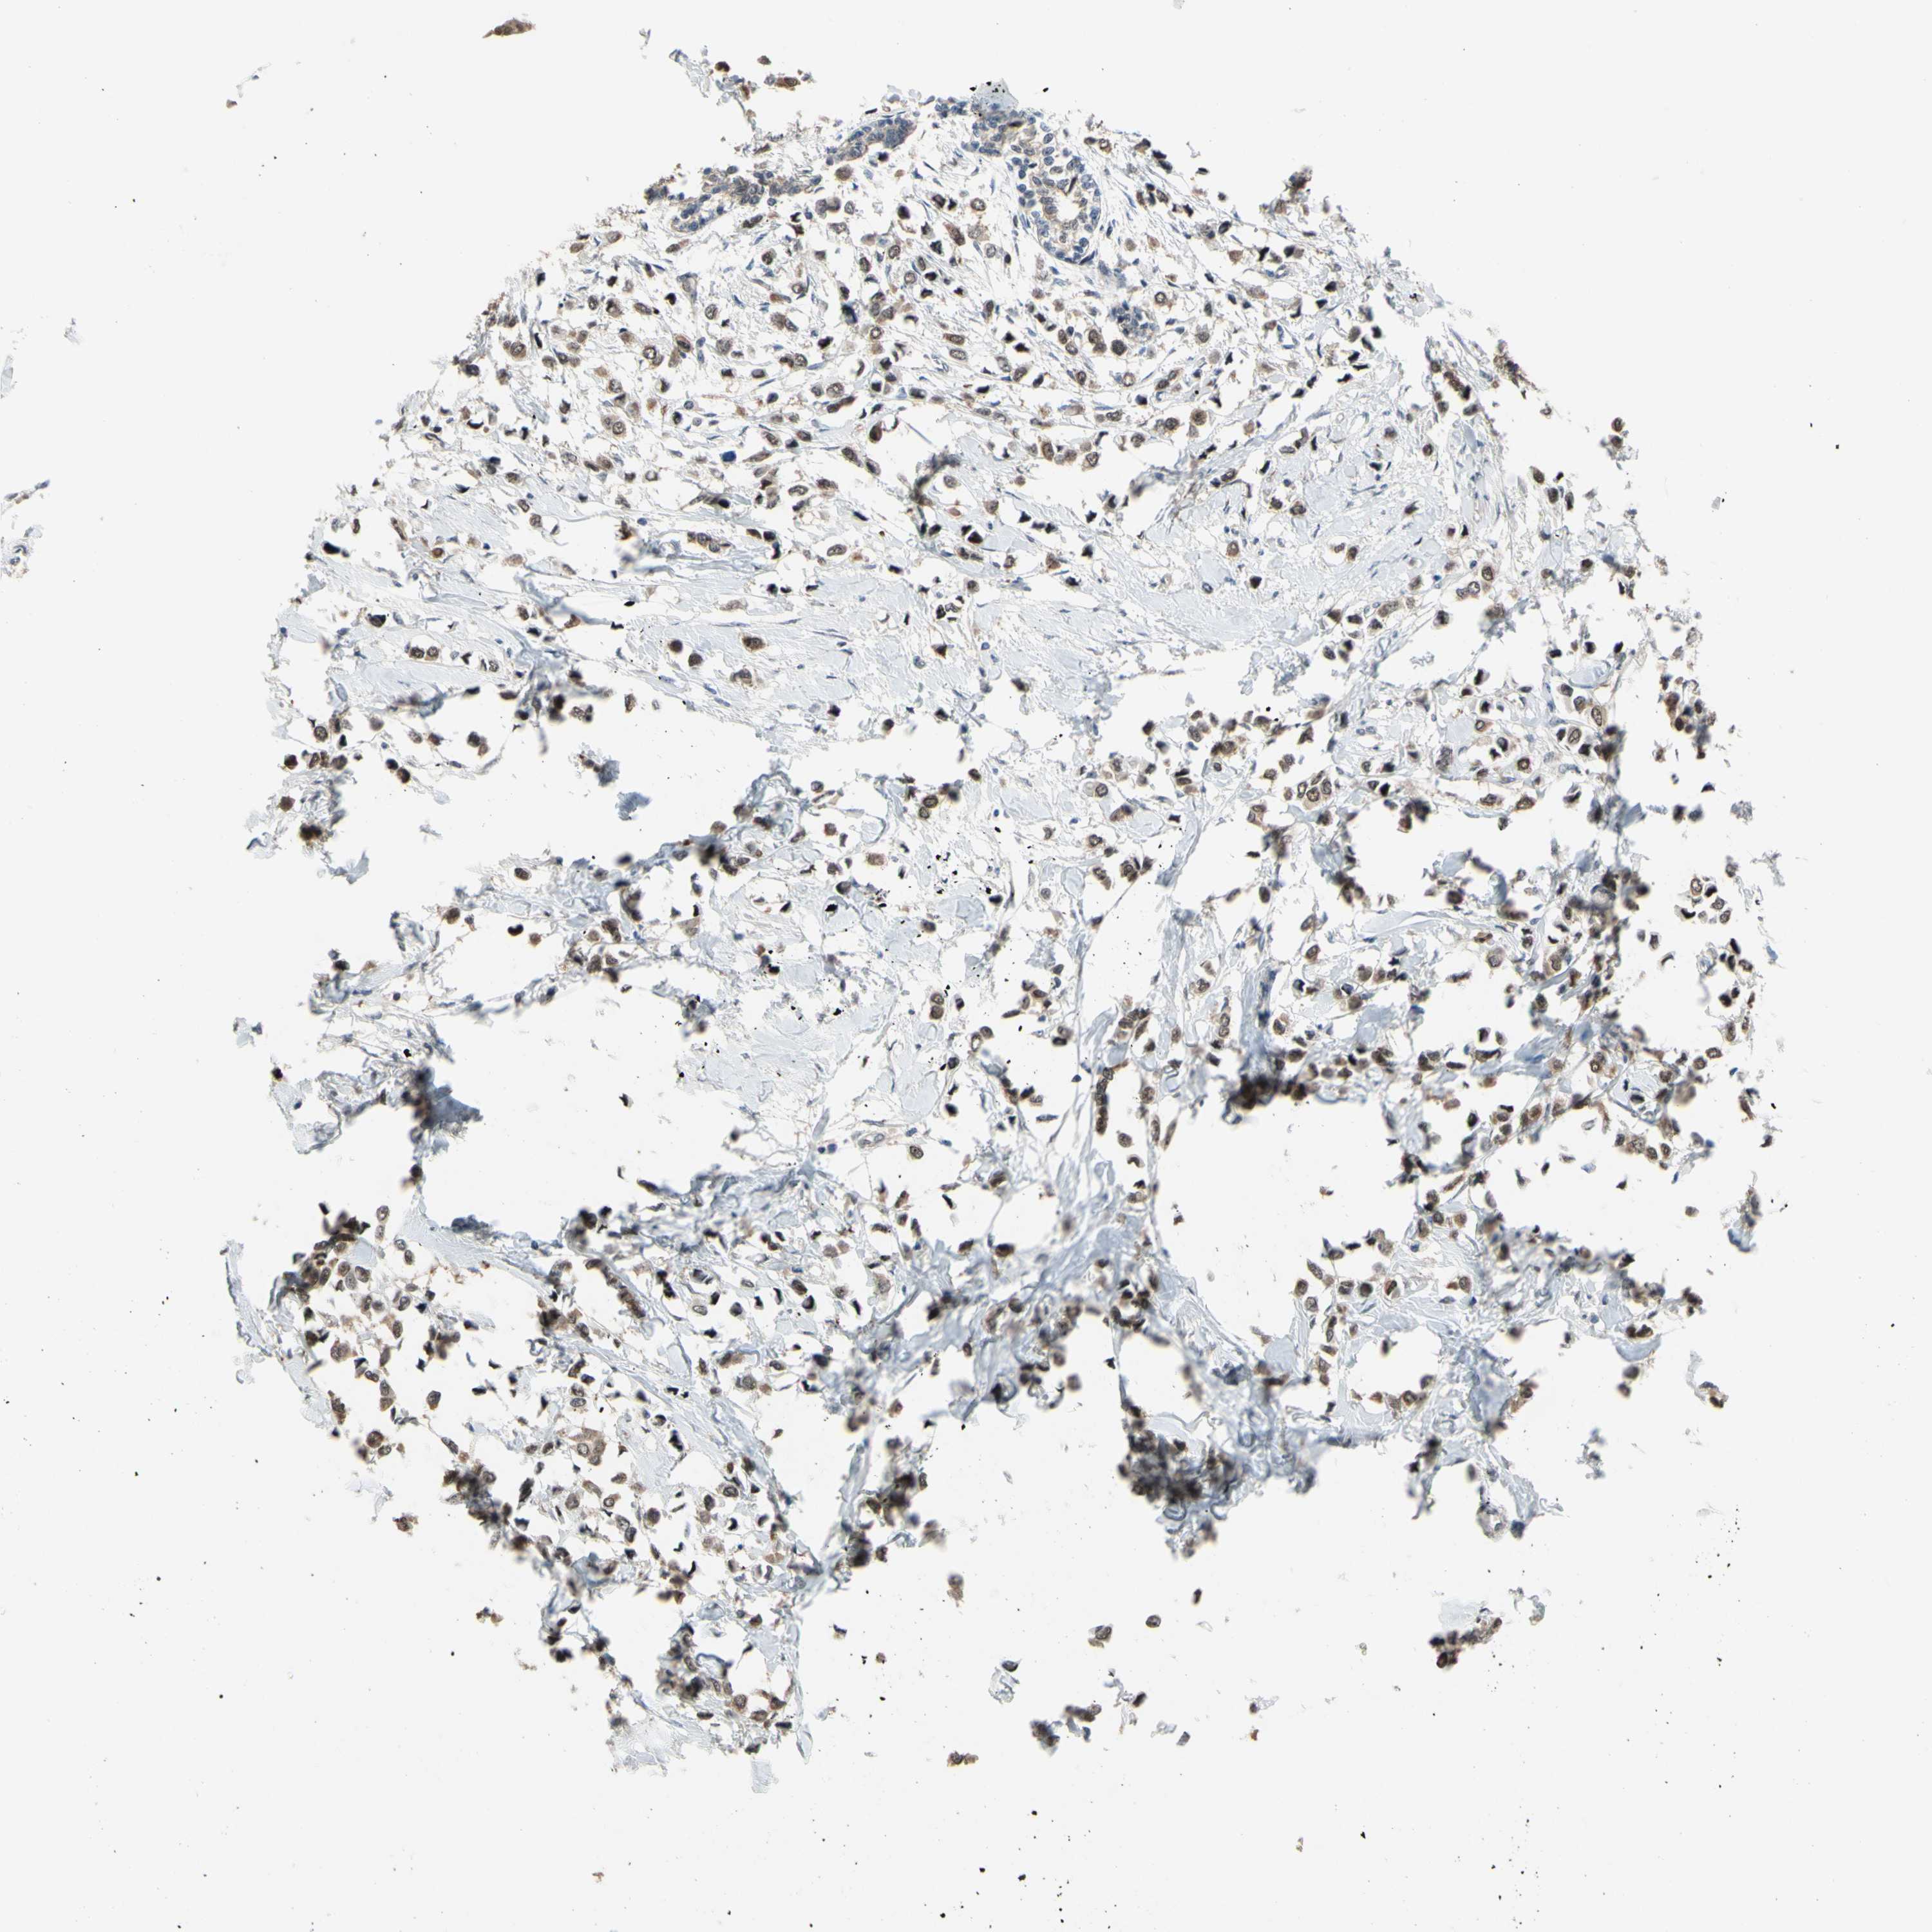

CANCER BREAST CANCER Show tissue menu

BRCA TCGA BRCA VALIDATION PROTEIN EXPRESSION